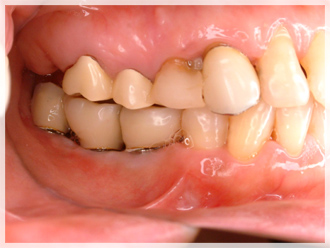

インプラント治療 症例のご紹介3 F様

複数本のインプラント治療 治療前・治療中・治療後のご紹介です。

下顎へ3本のインプラントを埋入いたしました。

治療後の写真をご覧いただくと、他の歯と全く違和感がないのが分かります。

| 治療中 | 治療後 |